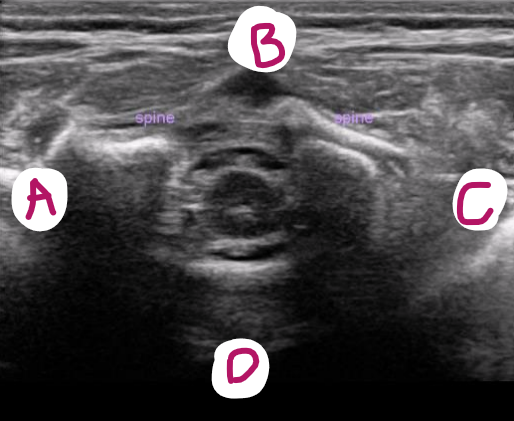

a

right

b

posterior

c

left

d

anterior